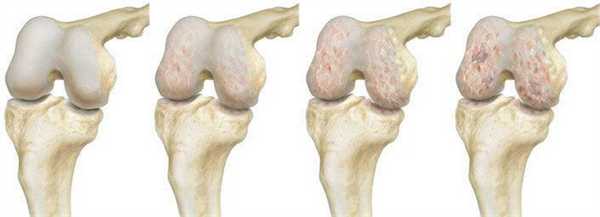

Костно-хрящевые структуры колена, приводящие в движение коленный сустав и отвечающие за опороспособность конечностей, - это самые уязвимые анатомические компоненты, которые поражаются артрозами. Эндопротезирование эффективный способом восстановления опорно-двигательного аппарата, которая подверглась серьезной дегенеративно-дистрофической агрессии на фоне хронического артроза.

Динамика разрушения хрящевой поверхности.